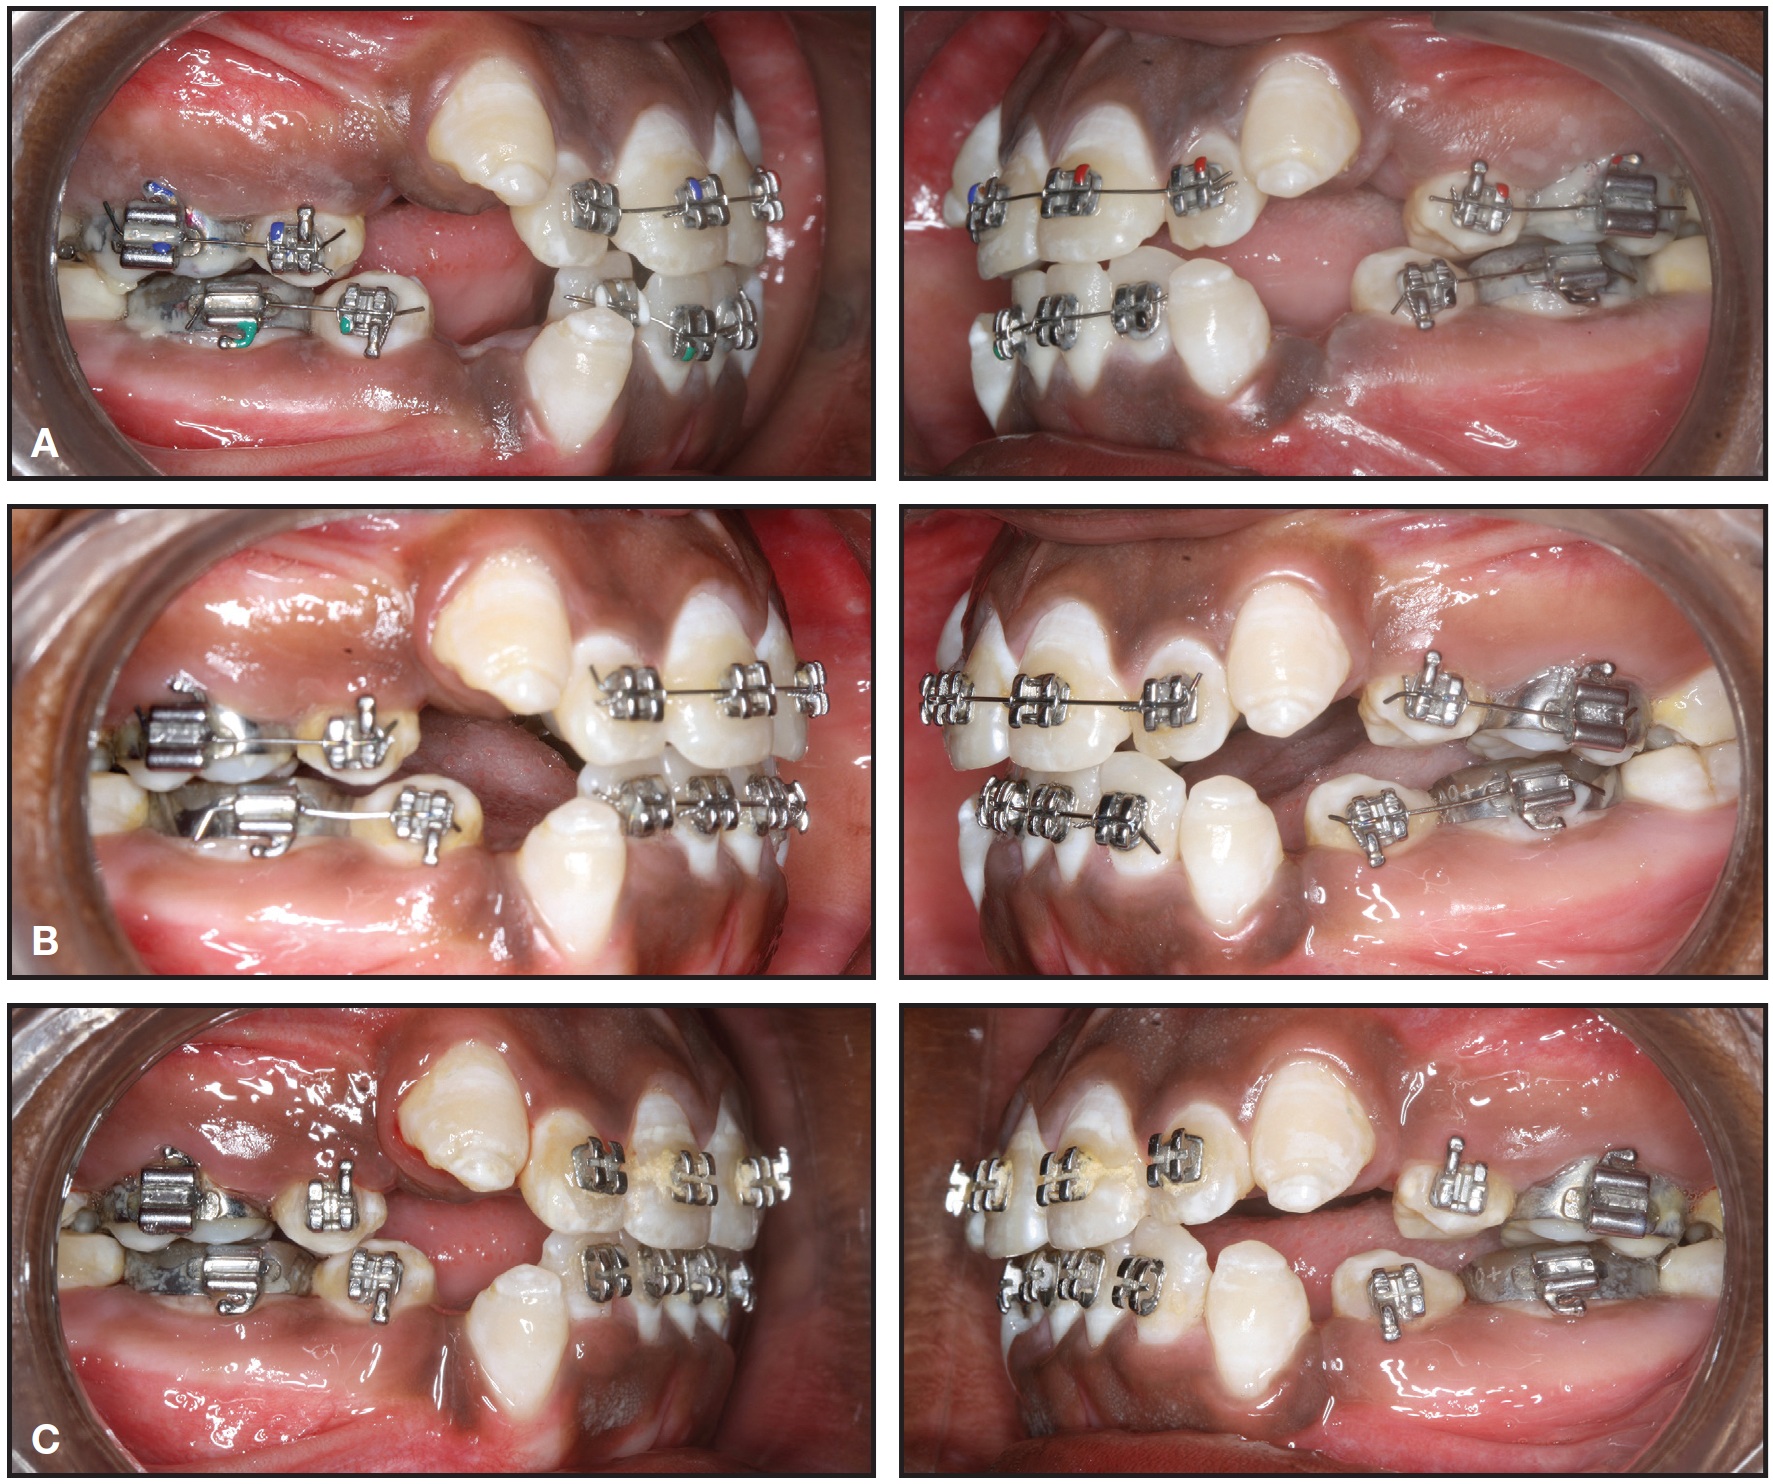

Fig. 5 Case 2. Sequential drifting of canines after one (A), two (B), three (C) months of treatment with MBT fixed appliances, transpalatal arch, and nickel titanium archwires.

Fig. 5 (cont.) Case 2. Sequential drifting of canines after four (D) and five months (E) of treatment with MBT fixed appliances, transpalatal arch, and nickel titanium archwires.

The treatment plan was to extract the upper first premolars and use driftodontics with group B anchorage in the upper arch. All maxillary teeth except the canines were bonded with .022" MBT brackets, and the incisors were aligned with segmental mechanics on .014" and .016" nickel titanium archwires. The canines were allowed to drift into the extraction spaces without any direct force application (Fig. 5).